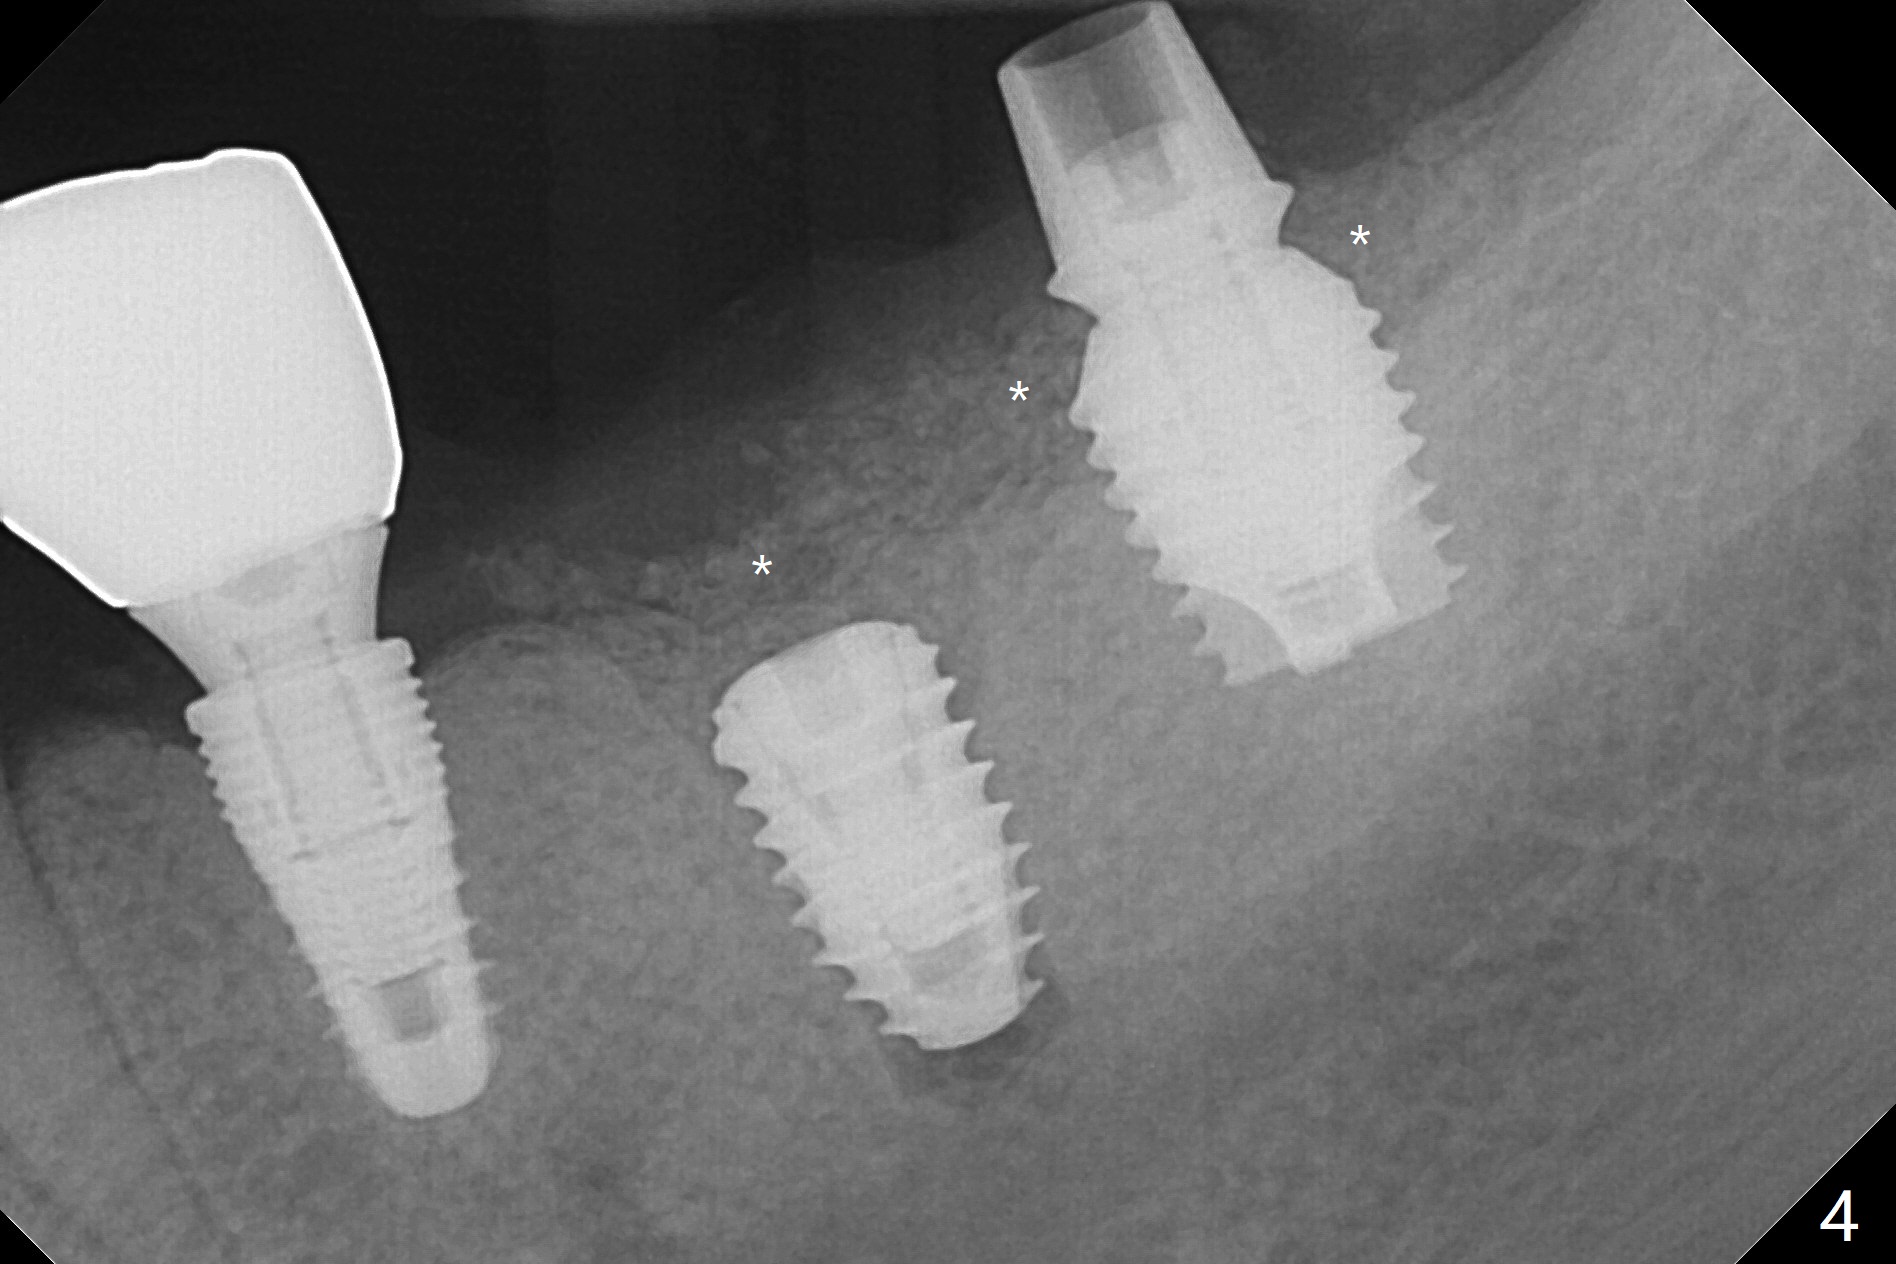

Since there is ~ 2 mm bone apical to the 5x8 mm loose implant at #19 (Fig.1), primary stability is achieved for a 4.5x10 mm dummy IS implant (having better surface treatment than the previous implant) when osteotomy is finished with a 4 mm drill (Fig.2). It is the same associated with a 4.5x7.3 mm definitive one with apical space (Fig.3 *). After depth adjustment to make sure that the implant is subcrestal circumferentially, sticky bone is placed on the top of the implant and around the implant at #18 (Fig.4 *), followed by PRF membranes and suturing with 5-0 PGA and 4-0 Chromic gut suture. Periodontal dressing is applied around the cemented abutment at #18 for additional retention. There is no paresthesia postop. In fact immediate implant redo is fairly safe. The wound heals 1 month postop (Fig.5). There is reorganized bone coronal to the healing screw 4 months postop (Fig.6), which is confirmed in uncovering. One month post uncover, the 6x4 mm healing abutment is found to be loose, suggesting incomplete seating after uncover. A 5.2x4.5(4) mm cemented abutment seems to be incompletely seated (Fig.7). It remains the same after 5.5 and 6.0 mm profile drills (Fig.8,9). A 4.5x4.5(4) mm abutment appears to be completely seated (Fig.10). When the crowns of #18 and 19 are cemented, the gingival embrasure between them is narrow (Fig.11 ^) because of bulky porcelain build-up (*). The tooth #21 with buccal Class V defect (Fig.12 *) seems to have occlusal trauma 1 year 6 months post cementation of #18 and 19. The problems are subsequently taken care of.